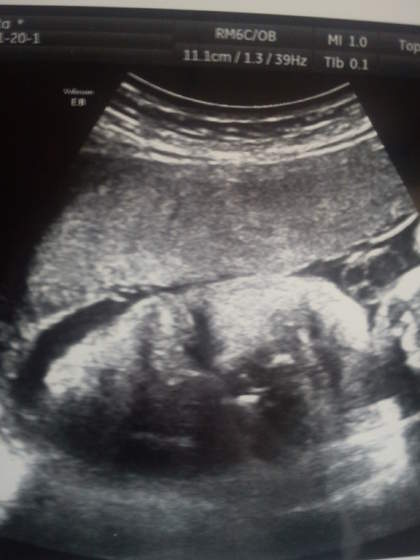

każda jedna kosteczka, żyłka zostały sprawdzone. Potwierdzone, że czekamy na wspaniałą, śliczną córeczkę

mała wszystko ma w normie/prawidłowe oprócz tych chol.... komór...:-( Komory powiększone.. na szczęście z tego co już zdążyłam wyczytać (tak tak google wygrało) jeżeli wszytko inne w normie to nie ma się czym martwić... niby tak, ale ja jakbym przestała żyć... tak się martwię :-( teraz zostaje nam modlitwa, że jak pojedziemy za 3 tyg to nie będą powiększone a nawet wręcz się zmniejszą... Doktorka powiedziała, że w/g niej to albo po przeziębieniu (proszę dziewczyny uważajcie na siebie!) jeżeli było wirusowe i nie wzięłam antybiotyku albo ... coś zjadłam nie takiego

I jeszcze jedno.. pisałam kiedyś, że u mnie był problem z ustaleniem miesiączki bo po zastrzykach to miałam nie miałam- nawet nie notowałam... na opisie mam "przepływ tt pępowinowych powyżej normy dla tego okresu ciąży S

3,43" ale z tego co z mężem zrozumieliśmy to ciąża może być do 2 tc młodsza niż myślimy... już sami nie wiemy co myśleć